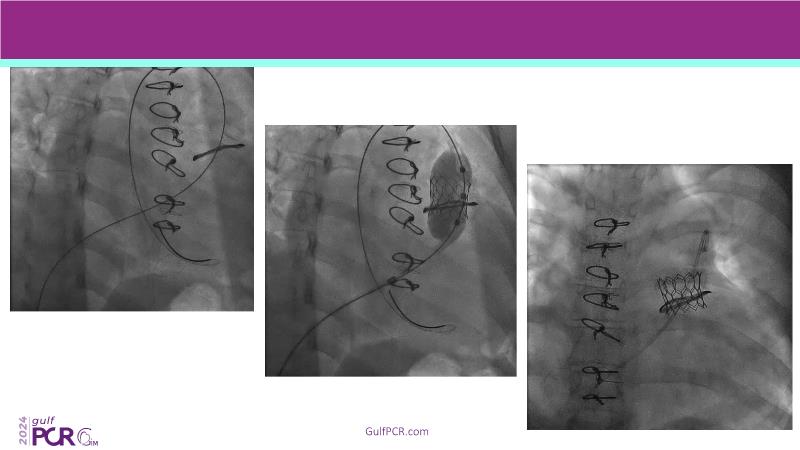

Stay ahead in TAVI innovation by exploring the advanced balloon-expandable Myval THV series. This session highlights the latest clinical data, optimal sizing and implantation techniques, and valuable real-world insights, including long-term follow-up results.

- To learn about the novel balloon expandable Myval THV series and the up-to-date clinical evidence for it

- To understand the best practices for Myval sizing and implantation technique for best outcomes